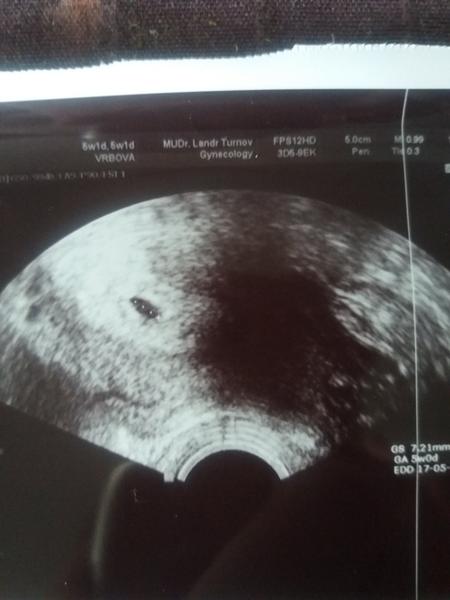

@shi_sha ja jsem taky chtela cekat do 7tt, volala jsem a ptala jsem se a rekla mi at prijdu hned at se mrknou jestli je tam kde ma byt. Takze mam fotku bublinky 5tt a za 14dni mam prijit na srdicko.